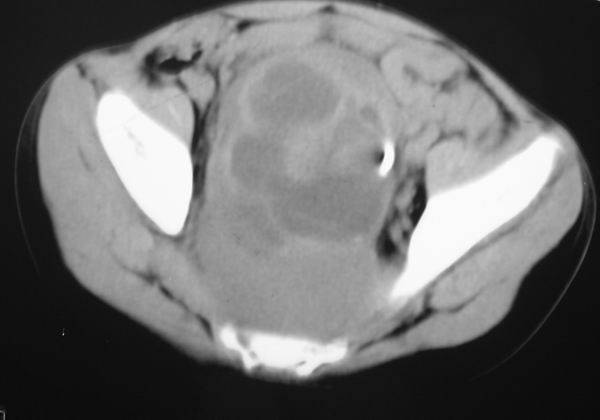

标题: PED0321:F 7 骶尾部肿瘤 有病理结果 [打印本页]

标题: PED0321:F 7 骶尾部肿瘤 有病理结果

骶尾部肿瘤 有病理结果

畸胎瘤

考虑畸胎瘤可能性大。骶尾骨无破坏。不考虑脊索瘤。

骶骨没有发现骨质破坏,畸胎瘤的可能性大